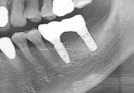

• Case1

• Case2

• Case3

• Case4

• Case5

• Case6

• Case7

• Case8

• Case9

• Case10